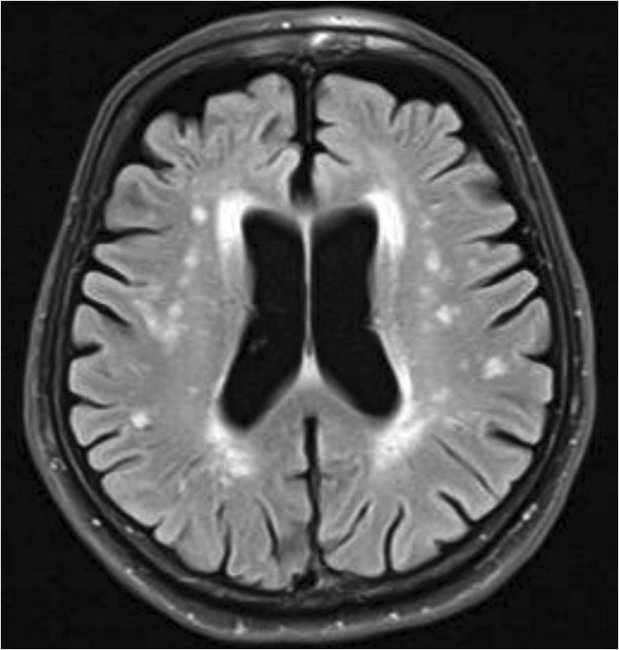

Рисунок 2. Конструктивный праксис. Тест рисования часов

Дополнительные методы исследования: рутинные анализы крови и мочи – без патологии. Биохимический анализ крови: холестерин – 7,2 ммоль/л, липопротеиды низкой плотности – 4,2 ммоль/л (норма – 0–2,6), уровень глюкозы в крови – 5,5 ммоль/л. ЭКГ: признаки гипертрофии миокарда. Дуплексное сканирование магистральных артерий головы: признаки стенозирующего атеросклероза бифуркации левой общей сонной артерии и устья левой внутренней сонной артерии 45%, правой общей сонной артерии 45%, бифуркации правой общей сонной артерии 50%. Стеноз правой позвоночной артерии до 40%, левой – до 50%. МРТ головного мозга (рис. 3): расширение боковых желудочков и ликворных пространств (признаки атрофии вещества головного мозга), умеренный субкортикальный и перивентрикулярный лейкоареоз.

Рисунок 3. МРТ головного мозга пациента М.

Представлен клинический пример безынсультного формирования СКР. О сосудистом характере КР свидетельствует: длительный анамнез неконтролируемой артериальной гипертензии, гиперлипидемия, курение, злоупотребление алкоголем в анамнезе, абдоминальное ожирение (окружность талии > 110 см), гемодинамически незначимый (< 70%) стеноз церебральных артерий; наличие в неврологическом статусе типичных признаков хронической сосудистой мозговой недостаточности, таких как псевдобульбарный синдром, пирамидная недостаточность, нарушение походки по типу лобной дисбазии; клинические особенности нейропсихологических расстройств: на первый план выходят психическая замедленность, нарушение организации деятельности (например, ошибки в тесте рисования часов), трудности обобщений при негрубых нарушениях памяти, сохранной ориентировке; данные МРТ головного мозга, которые выявляют выраженное цереброваскулярное поражение. СКР в данном случае формируются без клинически очерченных инсультов, т. к. в их основе лежит патология сосудов небольшого калибра (гипертензивная микроангиопатия). Проявления СКР у пациента сочетаются с некогнитивными симптомами: флуктуирующим нарушением поведения (раздражительность, агрессивность), апатией, эмоциональными расстройствами в виде субклинической тревоги и депрессии. Эмоционально-поведенческие расстройства нередко дезадаптируют пациентов даже больше, чем снижение познавательных функций. Сочетание депрессии, апатии, нарушений поведения и КР прогностически неблагоприятно, поскольку пациенты невнимательно относятся к назначениям врачей, не выполняют их рекомендации, что, в свою очередь, может привести к последующим нарушениям мозгового кровообращения [21]. Сочетание КР и некогнитивных симптомов при хронической сосудистой мозговой недостаточности объясняется тем, что они имеют общую патофизиологию в виде нарушения связей между подкорковыми структурами и лобной корой с развитием вторичной лобной дисфункции [22, 23].